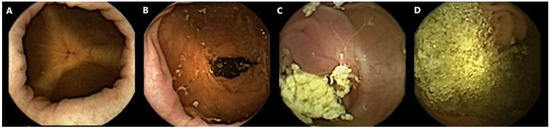

All capsule videos were analyzed using PillCam™ reader software v9 (Given Imaging Inc., Duluth, GA, USA). A gastroenterologist with extensive experience in SB capsule endoscopy (CE) and CCE evaluated cleanliness on the 4-point Leighton–Rex scale [27]. The grades excellent and good were considered adequate, while the grades fair and poor were considered inadequate (Figure 1). The reader was blinded to the bowel preparation regimen used. Complete CCE was defined as visualization of the hemorrhoidal plexus or an excreted capsule. The transit times were calculated for the stomach, SB, and colon separately by PillCam™ reader software.

Figure 1.

Examples of colon capsule video frames graded according to the Leighton–Rex scale. (A) Excellent. (B) Good. (C) Fair. (D) Poor.